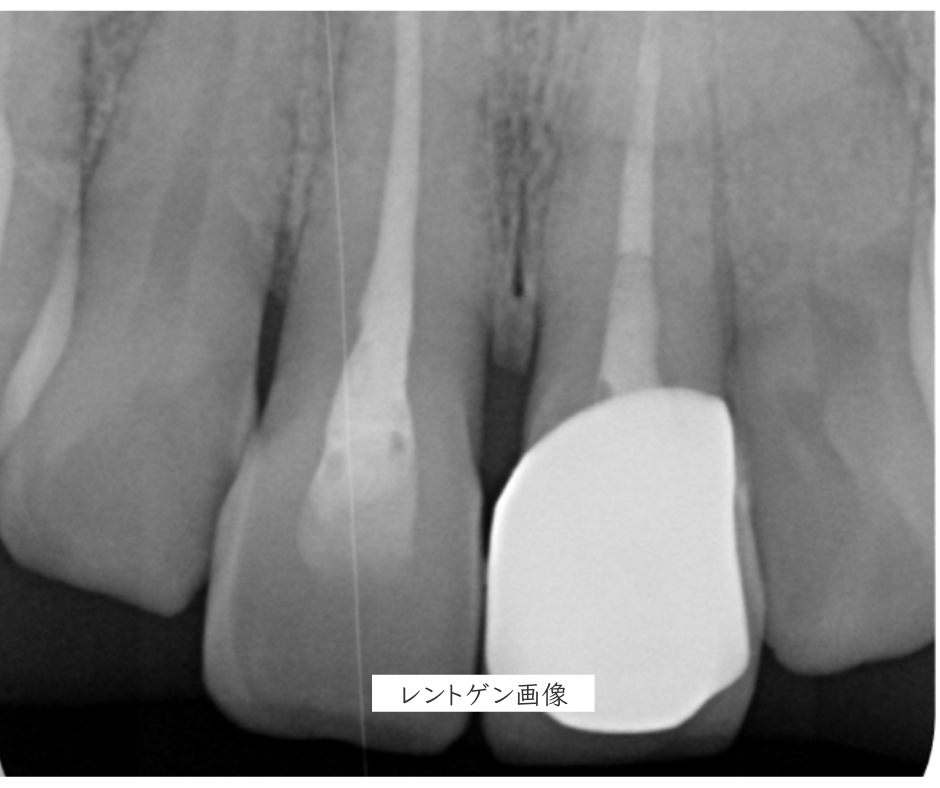

※名古屋RD歯科クリニックでの症例

術前

治療前の患歯のレントゲン画像です。患歯である前歯2本には、歯の根(根管)の中に人工物が充填されているため、レントゲン画像では白く映し出されています。